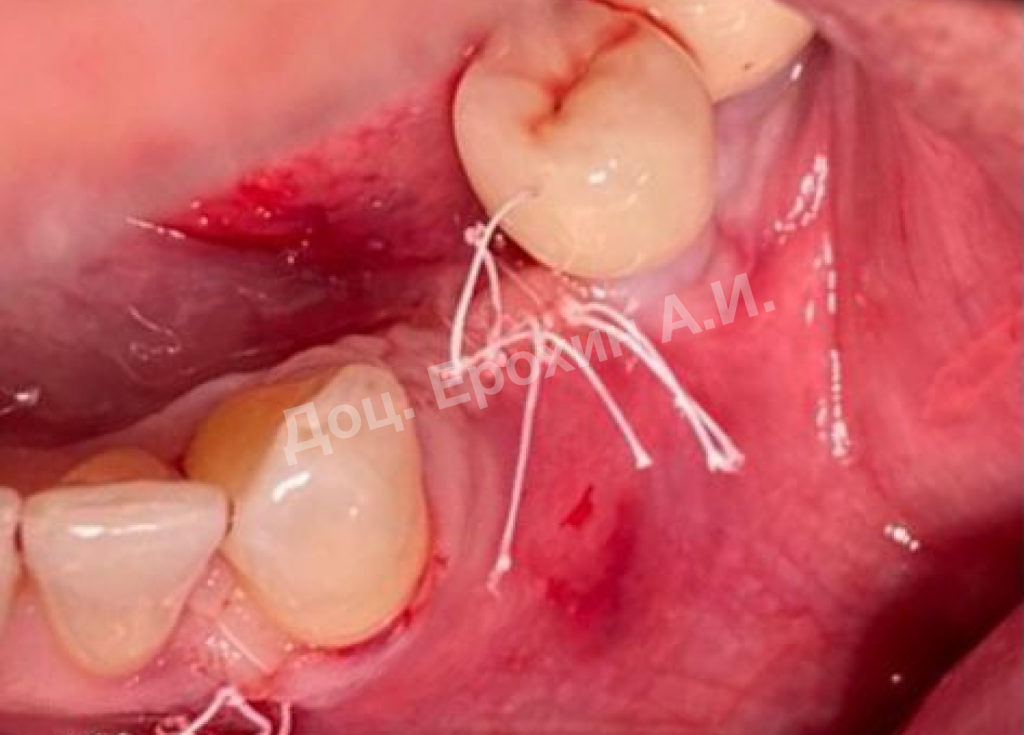

Вертикальные аугментации — самый непредсказуемый тип костной пластики методом НРТ. Мембрана способна коллапсировать, смещая в апикальном направлении костный материал, тем самым полностью нивелирую потраченные усилия.

Тентовые винты имеют широкие шляпки, которые позволяют мембране опираться на них, тем самым препятствуя изменению профиля регенерируемого участка.